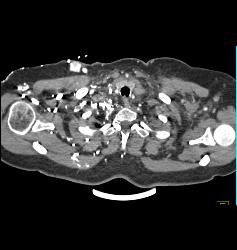

SVC Occlusion With Collaterals. SVC Occlusion Was Due to Tumor